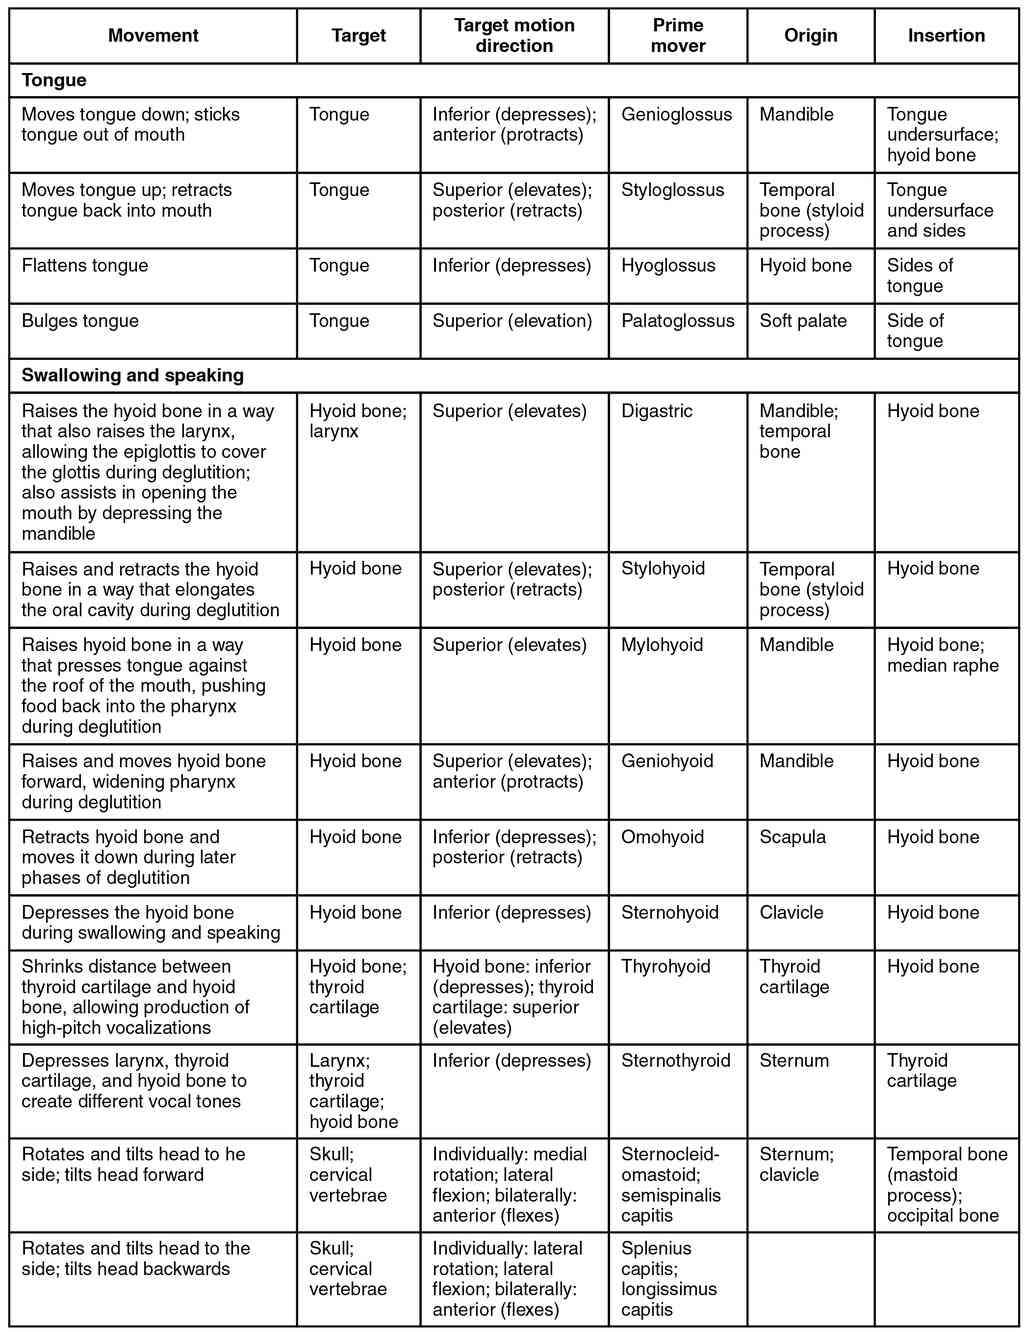

This page is under construction. For now, it is just a resource of the images found in the OpenStax Anatomy and Physiology Handbook. It wil slowly change into a revision tool. Each slide has a number. Use this to refer to the slide. When completed, it will have an unlabelled section, with labelled slides in parallel. On the unlabelled slides, write your answer and use the labelled slide to assess yourself. Keep track by also noting the number on each slide. Improvement at each attempt is important, more so than full marks on a first attempt.